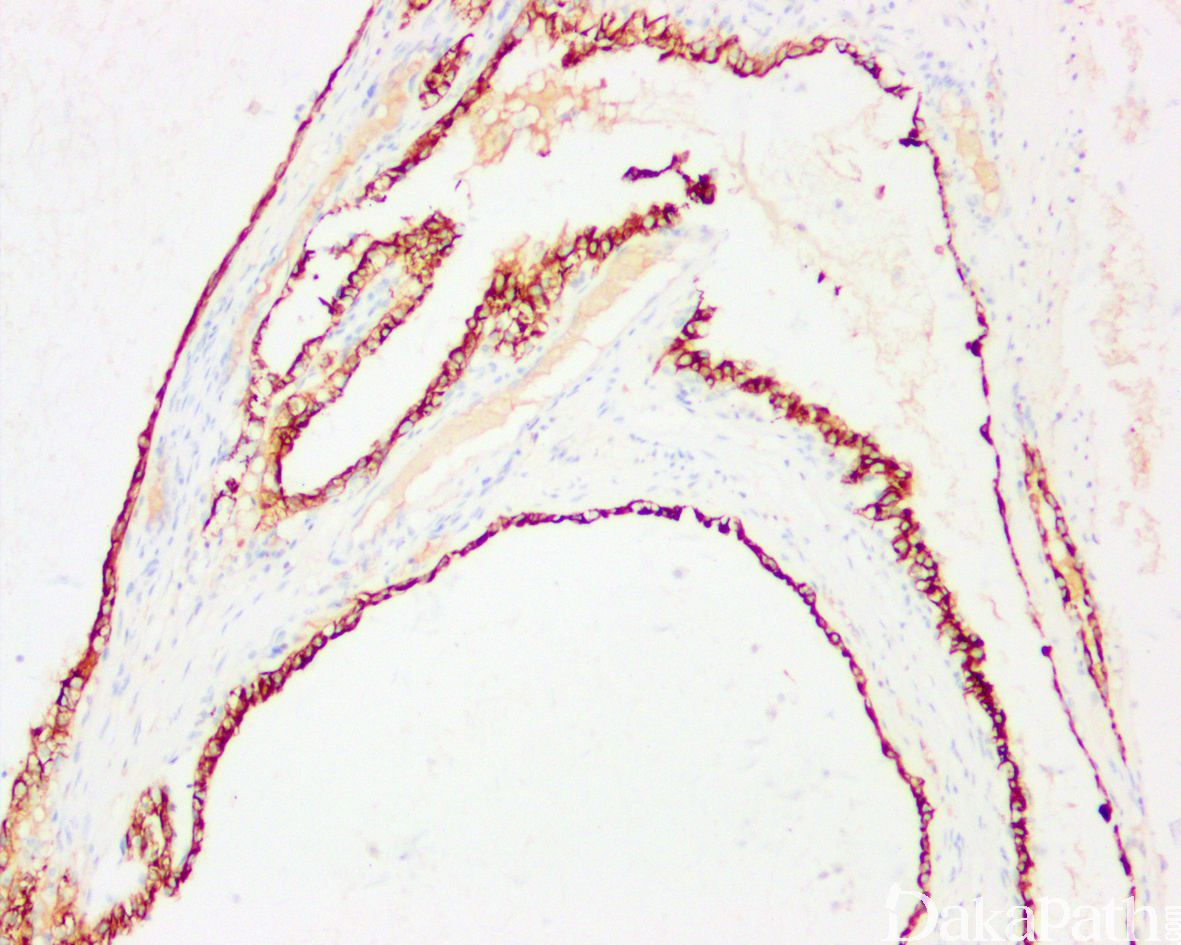

免疫组织化学染色:

PAX8 和 CAIX 强阳性,CK 和 EMA 阳性,CD10 局灶或弱阳性,CK7 部分阳性,cyclinD1. ck34be12 和组织细胞标记物阴性。